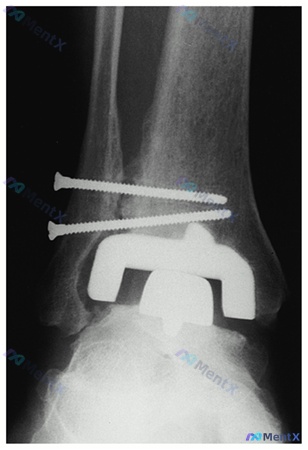

- X光片(图B):假体位置居中,假体周围无明显透亮带,螺钉位于骨皮质内

第一眼很容易盯着“假体”想问题,但前抽屉和内翻试验都是阴性,假体周围也没看到透亮线。

📋答案:该患者持续疼痛的最可能原因是:下胫腓联合骨不连/纤维愈合不良。